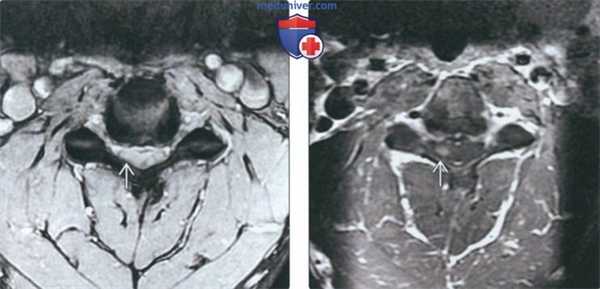

(Слева) На аксиальной КТ с КУ определяется тяжелый стеноз позвоночного канала, обусловленный диффузными грыжами диска на широком основании с сопутствующим обызвествлением диска. Определяется также выраженный двухсторонний стеноз межпозвонковых отверстий в сочетании с гипертрофией унковертебральных суставов и дегенеративными изменениями суставных отростков.

(Справа) На аксиальной MPT (Т2 ВИ) определяется выраженное истончение спинною мозга с относительно гиперинтенсивным сигналом, ограниченною спереди диском и остеофитами, сзади - утолщенными желтыми связками с гипоинтенсивным сигналом. Определяется выраженный стеноз обоих межпозвонковых отверстий.

(Слева) КТ с КУ, аксиальный срез: признаки тяжелого стеноза спинномозгового канала на фоне диффузного пролабирования межпозвонкового диска с вентральными грыжами и кальцификацией диска. Видны признаки выраженного двустороннего фораминального стеноза, гипертрофии унковертебральных суставов и дегенерации дугоотростчатых суставов.

(Справа) Т2-ВИ, аксиальная проекция: выраженное истончение спинного мозга, проявляющееся относительным усилением сигнала и связанное с его импинджментом между межпозвонковым диском и остеофитами вентрально и утолщенной отличающейся низкой интенсивностью сигнала желтой связкой дорзально. Также видны признаки выраженного двустороннего фораминального стеноза.